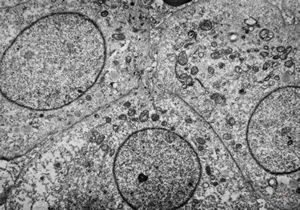

F,50y. | progressive multifocal leukoencephalopathy- viral particles in a glial cell

F,50y. | progressive multifocal leukoencephalopathy- viral particles in a glial cell

F,50y. | progressive multifocal leukoencephalopathy- viral particles in a glial cell